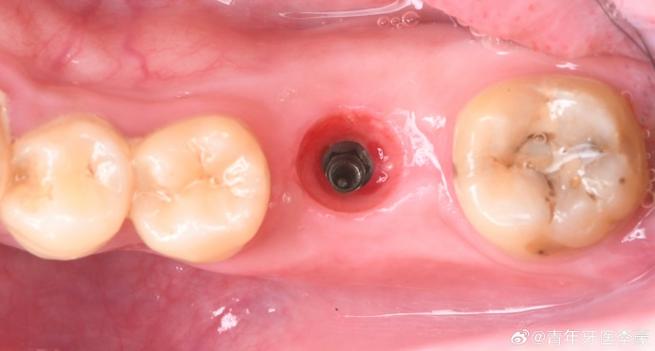

种植体植入后,种植体(相当于人工牙根)与周围牙槽骨之间没有形成良好的、稳定的骨结合(Osseointegration),或者结合不充分、不牢固。

这通常被称为种植体骨结合不良或种植体失败,这是种植牙成功的关键所在。

- 种植牙的核心是“骨结合”: 种植牙成功的基础是种植体(钛或钛合金制成)与牙槽骨之间形成直接的、功能性的结构连接和骨组织长入种植体表面的微观结构中(即骨结合),这就像把螺丝拧进木头里,木头纤维要长满螺丝的螺纹才能牢固。

- 初期稳定性不足: 种植体植入后晃动过大,无法提供稳定的界面让骨细胞附着。

- 临床检查: 种植体周围牙龈有无红肿、出血、溢脓、种植体有无松动、叩痛。

- 影像学检查: 拍摄X光片(根尖片或曲面断层片)是关键! 可以观察种植体周围骨组织的密度、有无骨吸收(暗影)、种植体与骨结合界面是否清晰,骨结合不良在X光片上可能表现为种植体周围出现透射暗影(骨吸收),或者种植体与骨之间界限模糊不清。